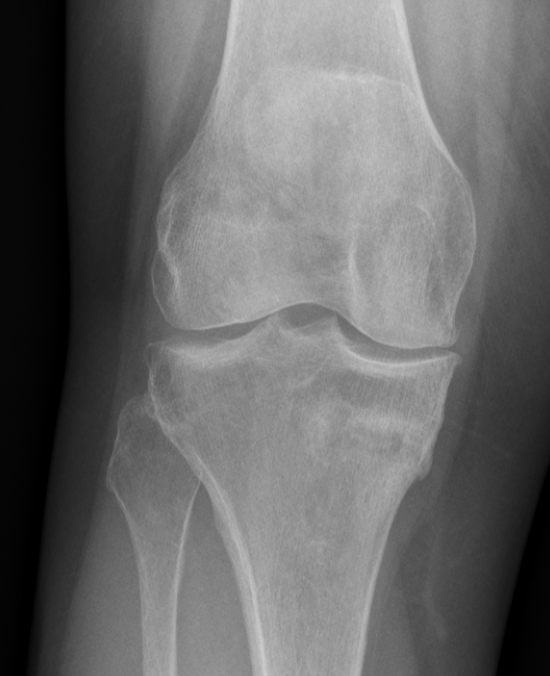

Healing medial tibial stress fracture